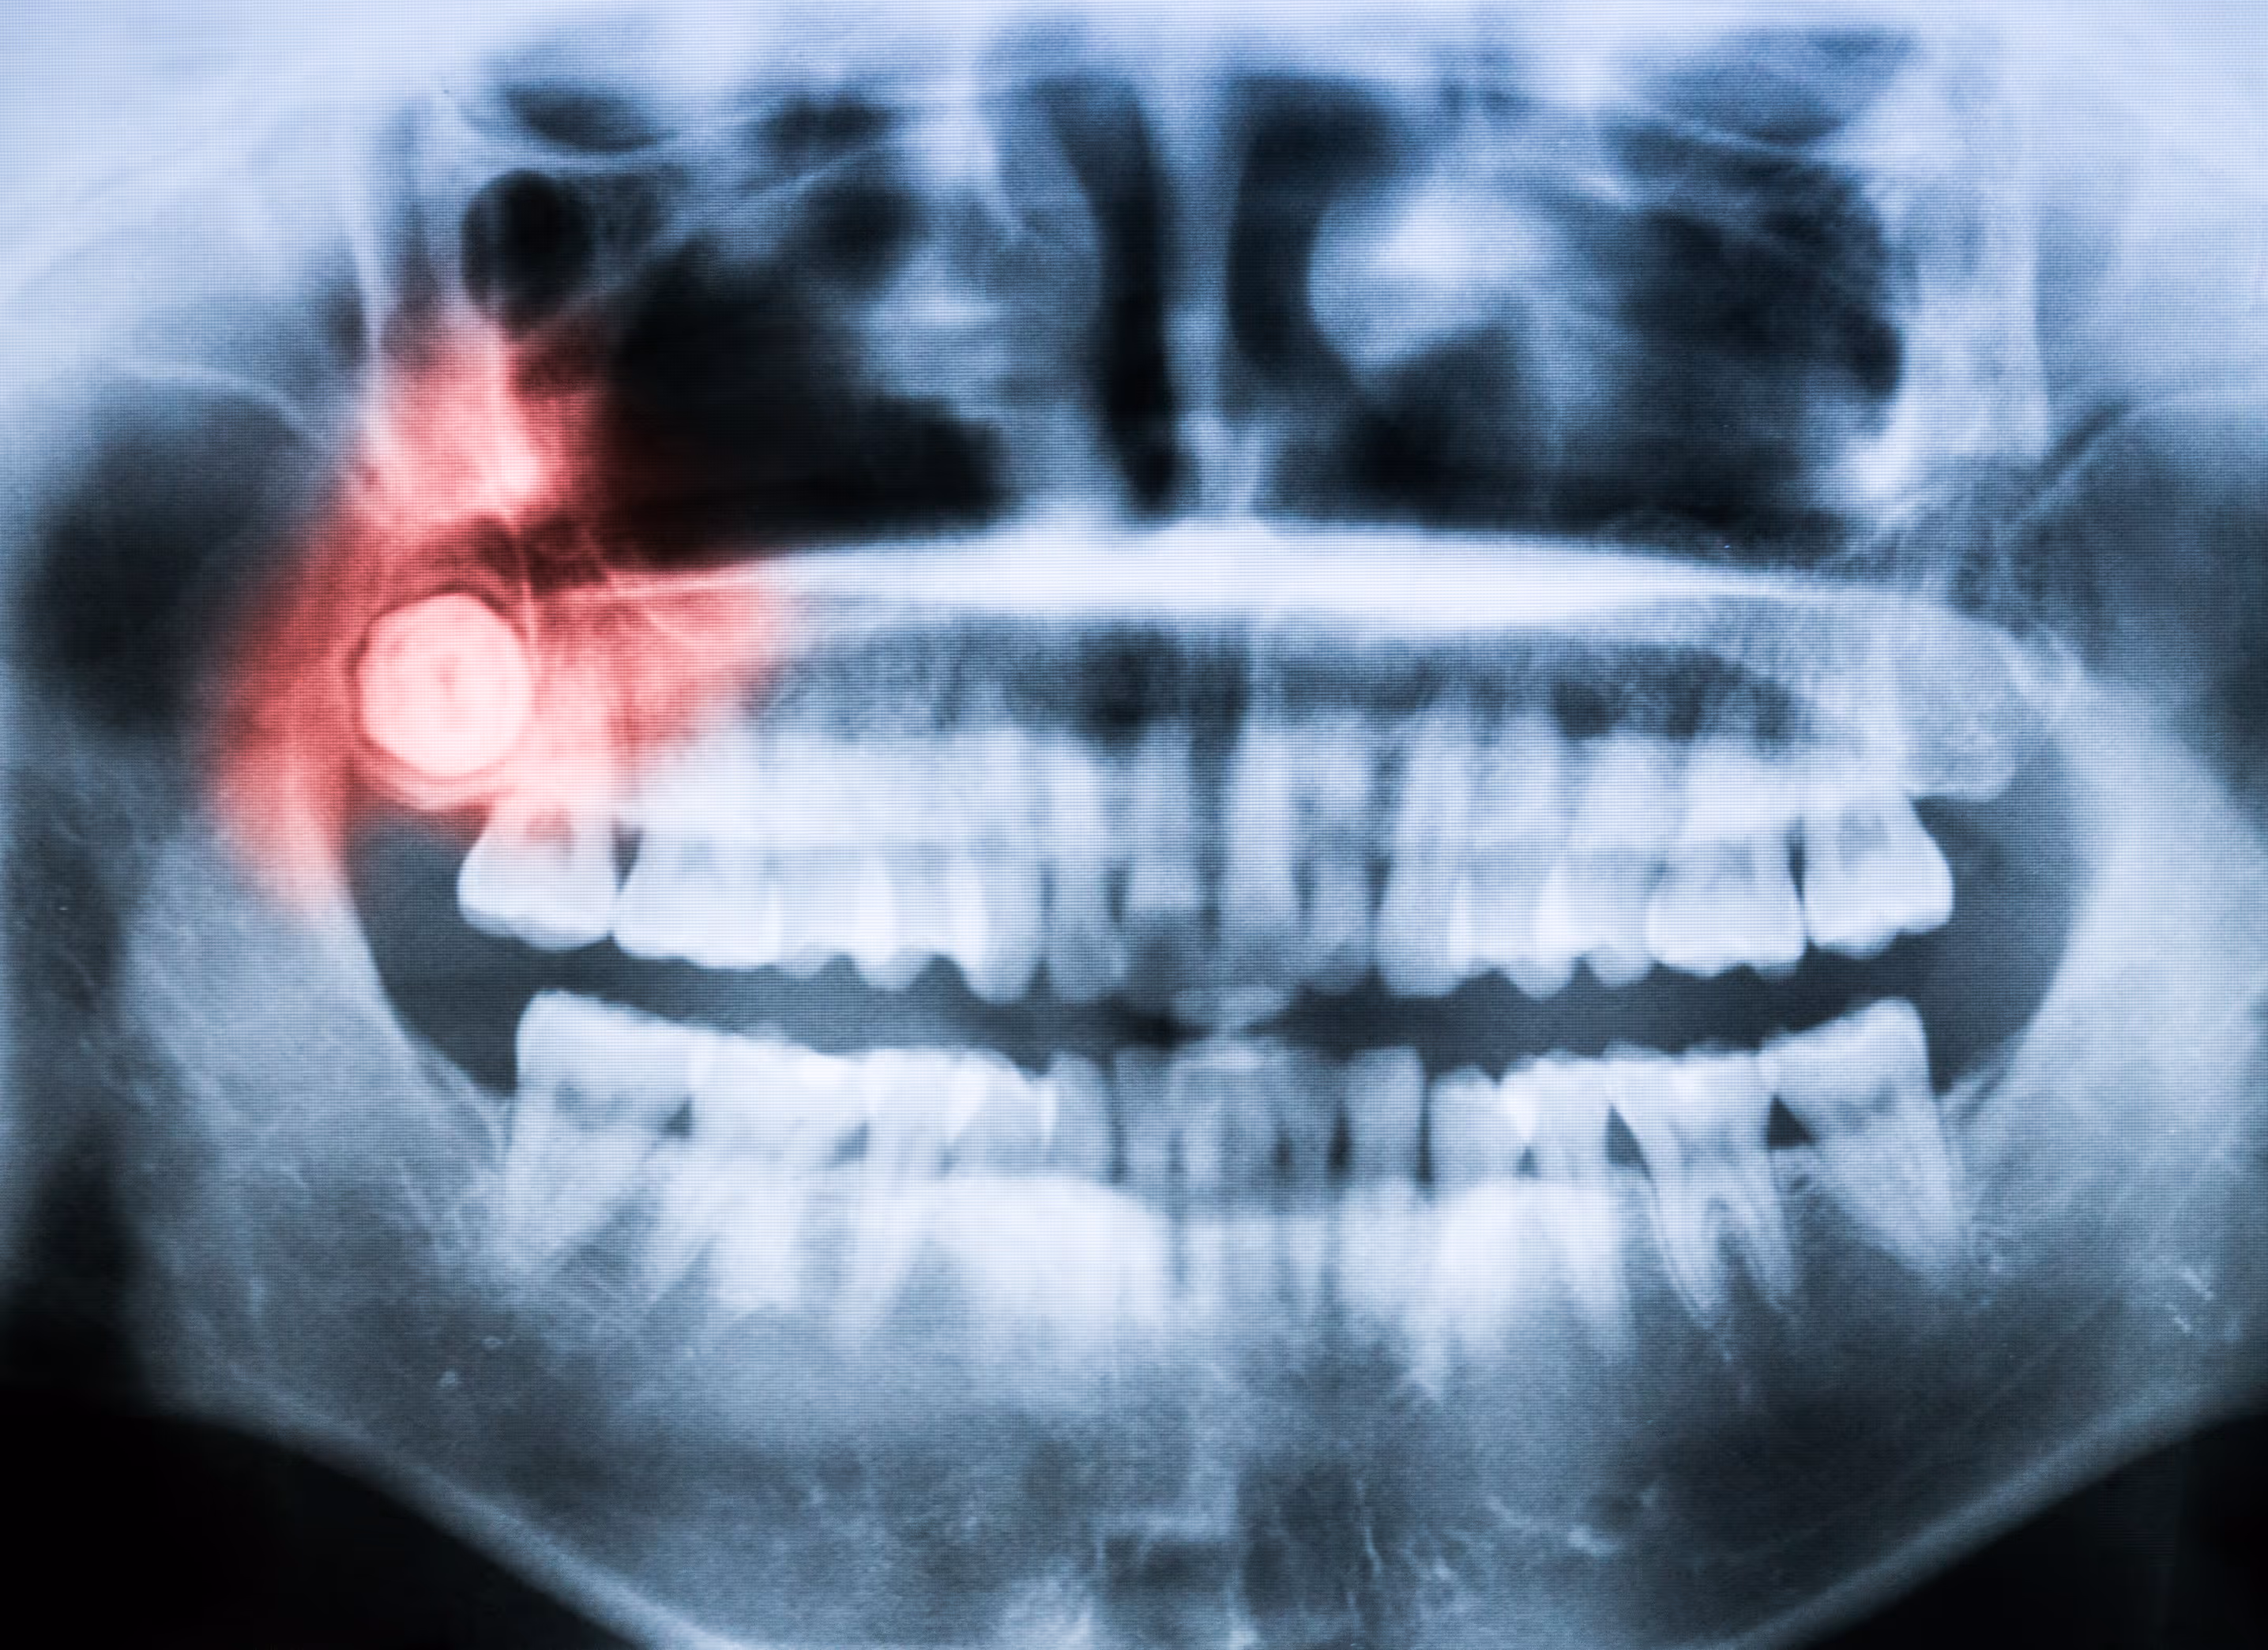

When children are infants, their baby teeth break through their gums and emerge from them. After a few years, those teeth start to fall out, and the adult teeth replace them. There are times when those adult teeth don’t erupt from the gums normally, and this can eventually lead to complications. If the tooth fails to emerge from the gums or comes in only partially, it is an impacted tooth.

Wisdom teeth are the ones that are most commonly impacted. These molars commonly come in when a patient is anywhere from 16 to 20 years old, but it can be later. These teeth often become impacted because they don’t have proper growth in the correct direction. There are various angles that they may grow in, and some even come in completely horizontally.

The jawbone generally isn’t big enough for the normal eruption of these teeth. Impaction is even more likely to occur in patients who have small jaws. When the impacted teeth aren’t removed, it can cause cysts to form in the area as well as infections that can be serious. It’s vital to get those impacted teeth removed for the good of your overall health.